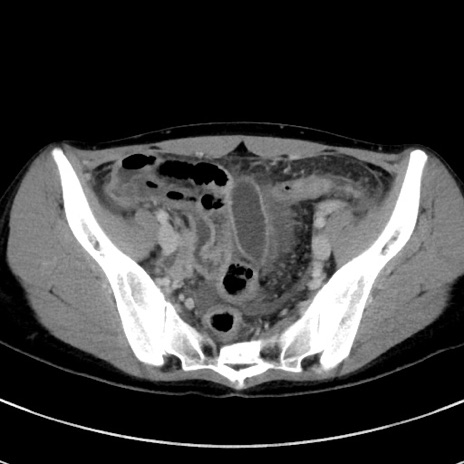

症例17(横断像)

【症例】20歳代女性

【主訴】嘔吐、下腹部痛

【現病歴】昨日夕食後に嘔吐し下腹部痛が出現。本日になっても嘔吐持続し改善しないため来院。

【身体所見】意識清明、BT 37.2℃、BP 108/67mmHg、腹部:平坦、やや硬、下腹部正中から右にかけて圧痛あり、反跳痛軽度あり、tapping pain(+)。

【データ】WBC 13600、CRP 14.94